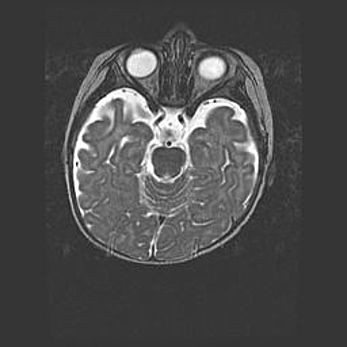

Церебральная ишемия II.

Возраст: 7 дней

Вес: 3350 г

Пол: женский

Окружность головы: 35 см

Срок гестации: 39 недель

Ишемия головного мозга – это состояние, которое развивается в ответ на кислородное голодание вследствие недостаточного мозгового кровообращения. У новорожденных она является следствием дефицита кислорода, что ведет к метаболическим расстройствам различной степени тяжести в тканях головного мозга, в том числе к развитию коагуляционных некрозов и гибели нейронов.